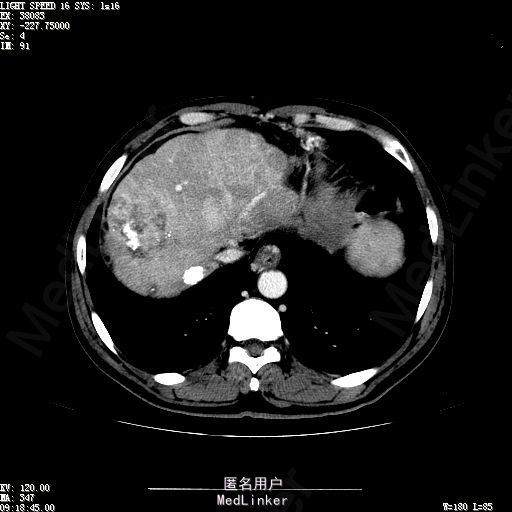

查体:生命体征平稳,神志清晰,发育正常,营养中等,体位自如,表情安静,无面容,配合检查合作。皮肤粘膜颜色正常,腹型平坦,无腹壁静脉曲张,未见胃肠型及蠕动波,无瘢痕,脐部正常。触诊:无压痛,无反跳痛,无腹肌紧张,无腹部包块。肝未触及,Murphy征阴性,脾未触及,肾未触及,无移动性浊音。 化验回报:血细胞分析(五分类):*白细胞计数 4.6 10^9/L、红细胞计数 4.27 10^12/L、血小板计数 100.0 10^9/L、血红蛋白 145 g/L、中性粒细胞百分比 68.6 %,*葡萄糖测定:葡萄糖 5.99 mmol/L,血清离子测定:*钾 4.46 mmol/L、钠 143.5 mmol/L,肾功能检测:*尿素 6.86 mmol/L、肌酐 84.2 umol/L,凝血五项:凝血酶原时间 10.7 秒、凝血酶原百分活动度 93.3 %,乙肝六项:乙型肝炎病毒表面抗原 阳性(+) 、乙型肝炎病毒e抗体 阳性(+) 、乙型肝炎病毒核心抗体 阳性(+) ,甲胎蛋白测定:甲胎蛋白 7146.00 ng/mL,ALT23U/L,AST42U/L CT检查如下图

诊断:乙肝肝硬化 静止性 代偿期 原发性肝癌 2型糖尿病 高血压病 下肢动脉闭塞征 诊断依据:1.有明确乙肝肝硬化病史 2.肝区隐痛,于外院发现肝占位,我院诊断肝癌,已行TACE治疗 3.查体:有肝掌 4.既往影像学提示肝内占位 处置:血管介入治疗:患者平卧位,以左侧肘窝为中心常规消毒、铺巾、利多卡因局麻。超声引导下,于肘横纹上方1厘米处确定皮肤穿刺点,改良Seldinger法逆行穿刺左侧肱动脉成功,置入5F血管鞘。沿导丝送入Cobra C2导管,送入降主动脉,将管头送入腹腔干,进一步送至肝固有动脉。造影见肝内广泛弥漫肿瘤染色,以右叶为主。以微导管超选肝右动脉,造影明确为肿瘤供血动脉,注入碘化油5毫升。退出微导管,经C2管注入奥沙利铂100毫克。退出C2管。拔出血管鞘,局部压迫10分钟。加压包扎。患者送返病房。